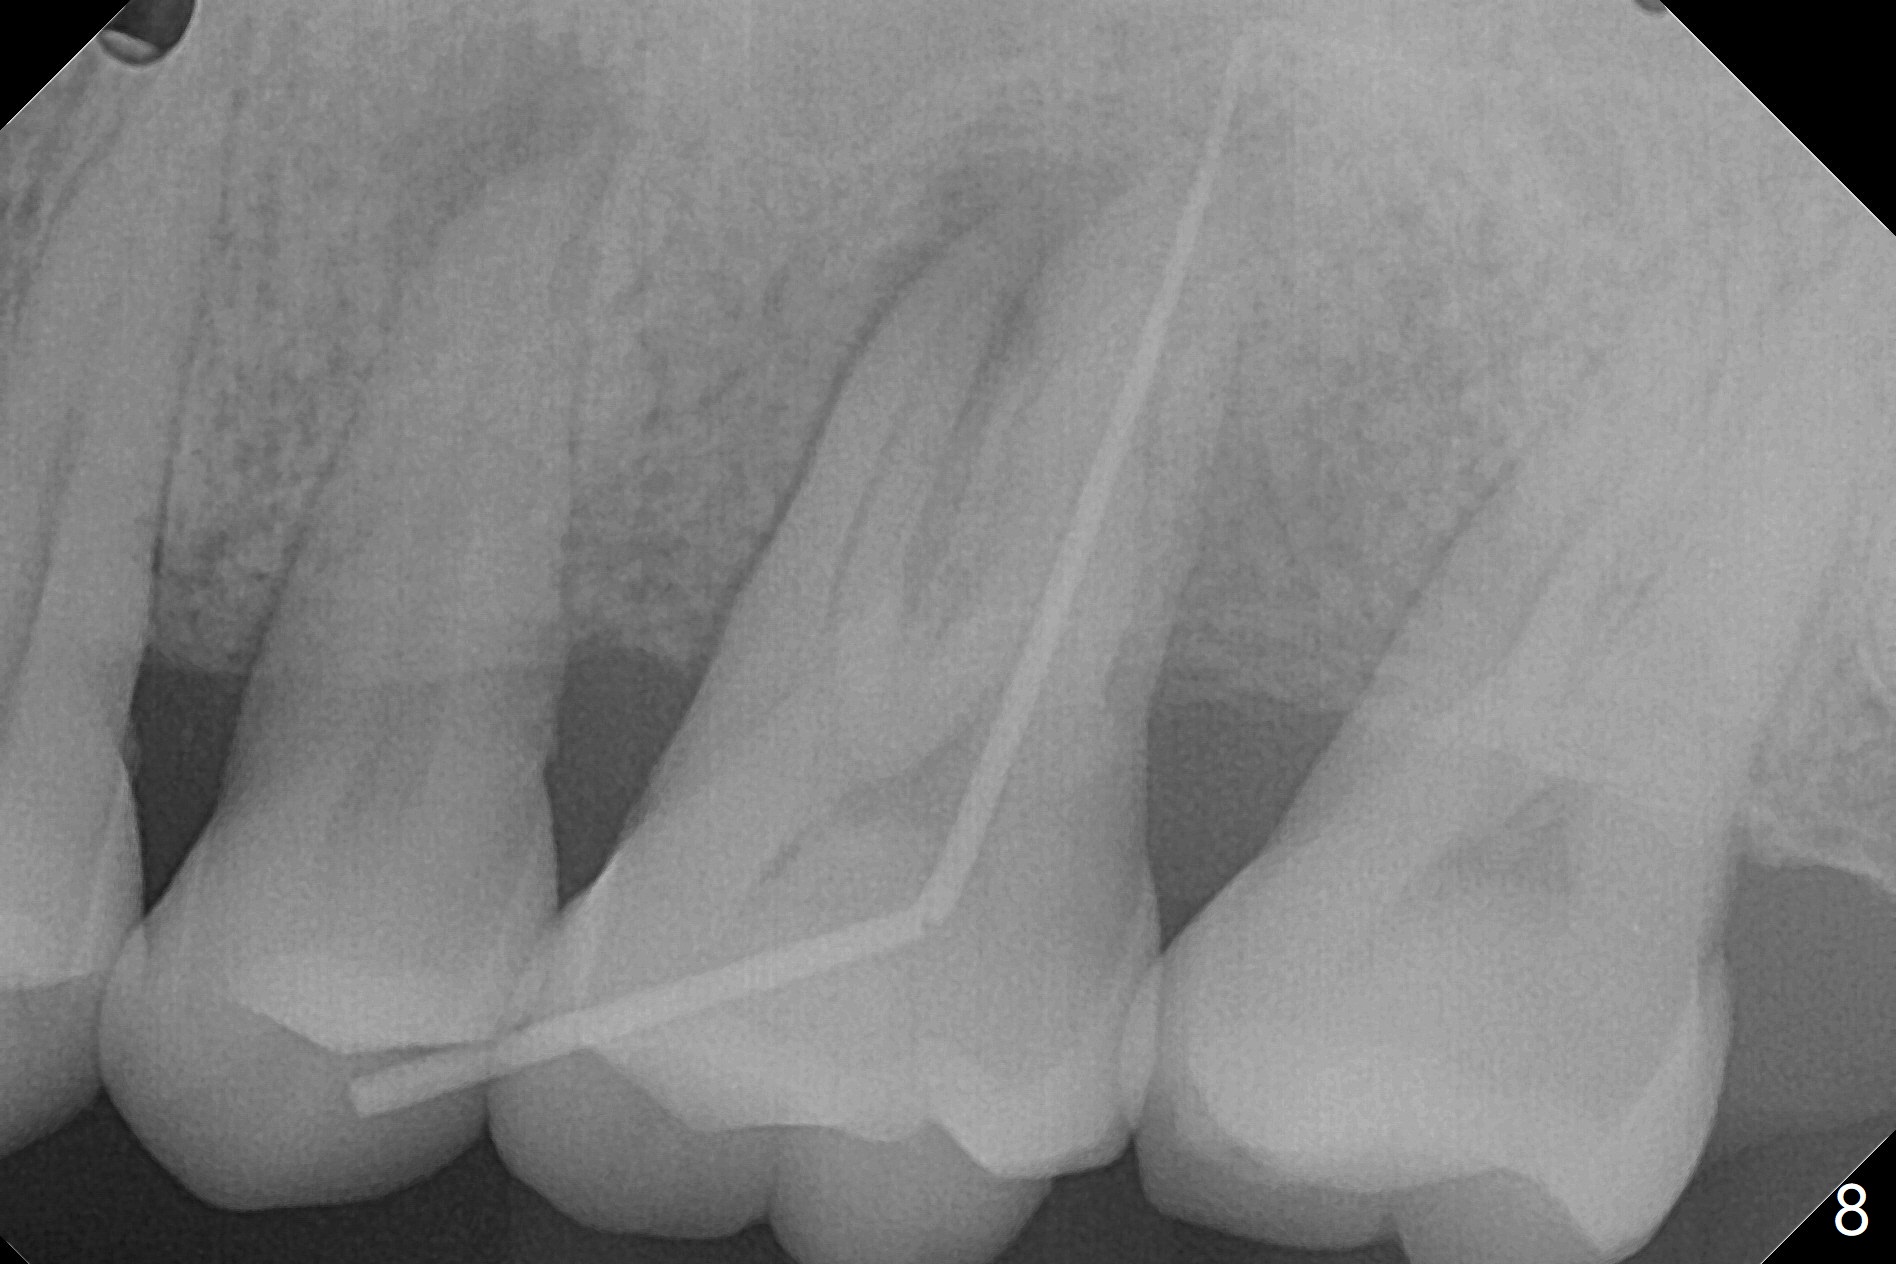

A 45-year-old man has chronic generalized moderate localized severe periodontitis; gingival recession is severe lingual of the tooth #14 with mobility II (Fig.1). The low bone density outline (Fig.1 white dashed line) is larger than the roots, suggesting lingual bone loss/low lingual crest. Although the bone height seems to be 11 mm (Fig.2), the bone responsible for primary stability of an implant will be apical (Fig.3 *,4). The implant platform will be ~3 mm subcrestal buccal, while ~3 mm supragingival lingual (Fig.5). The diameter of the implant will not be too large, 4.5 mm (dummy). There will be not biologic width issue. The large perimplant gap will be closed with sticky bone. Severe palatal gingival recession is shown pre- (Fig.6) and post- (Fig.7) SRP. #30 Gutta Percha inserted palatal reaches the highest point of the low bone density lesion (Fig.8). Pulpal test and CT will determine that endodontic treatment can regrow bone or that socket preservation is needed with Cytoplast.